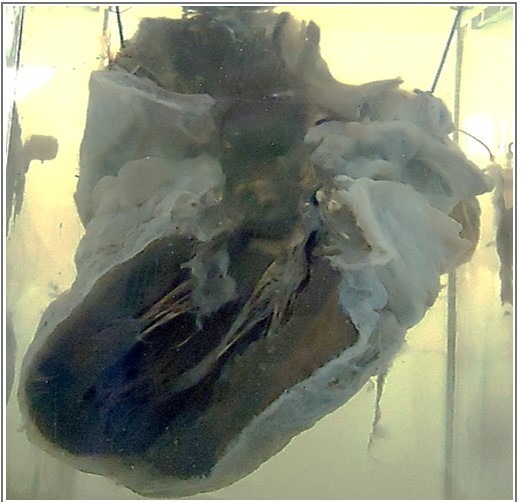

Q

what is this

A

heart with open left side

13

HEART is reduced in _________ with _______

1. The myocardium is _________ in color

2. PERICARDIAL FAT is replaced by ___________.

3. AORTA shows ____________.

size, tortuous coronaries

dark brown

edematous tissue

yellow atherosclerotic patches

14

diagnosis

brown atrophy of the heart

brown atrophy of pericardial fat

aortic atherosclerosis

from up to dowm

aorta

serous atrophy of fat

deep brown myocardium